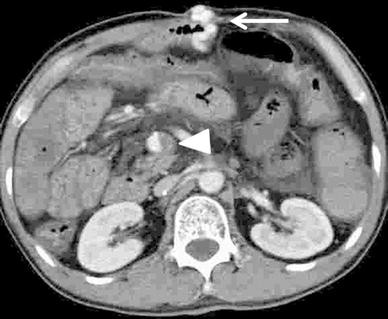

In the venous phase of superior mesenteric arteriography, we observed a collateral vein from the mesenteric varices to small abdominal wall veins (Fig. 2). We performed a surgical incision, and after inserting an 18-gauge plastic needle into an exposed abdominal wall vein we ligated a distal abdominal wall vein. We obtained retrograde CT images through the 18-gauge needle by manually injecting 5 ml of contrast medium (Iopamiron300; Schering Japan, Osaka) to visualize the mesenteric varices and extravasation into the small bowel (Fig. 3). The sclerosing agent was a 1:4 mixture of NBCA and iodized oil (Lipiodol; Laboratoire Guerbet, Roissy, France); this yielded radiopacity. The mixture of NBCA and lipiodol (1 ml) was injected slowly under fluoroscopic monitoring until the mesenteric varices were completely filled. The procedure was terminated when a CT scan acquired just after sclerotherapy demonstrated complete coagulation (Fig. 4).

Superior mesenteric arteriography (cone beam CT, venous phase) demonstrates mesenteric varices (arrowhead) from the jejunal vein (arrow) to a draining vein in the abdominal wall (open arrow)